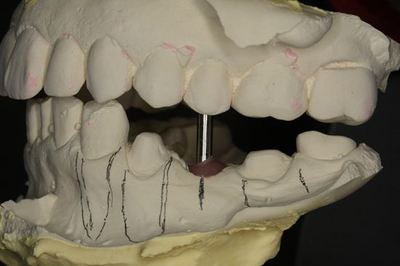

模型上で埋入ポジションのシミュレーションをします。

CTデータと重ね合わせて3次元的角度を決めます。